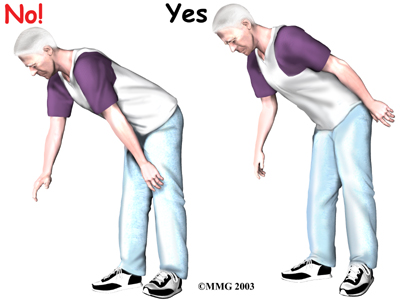

- Don't bend over past ninety degrees at the waist. Your hip may go past ninety degrees if you bend over at the waist to tie your shoes or pick up items off the floor.

Instead, use a reacher to put on your shoes and socks or to pick up items from the floor.